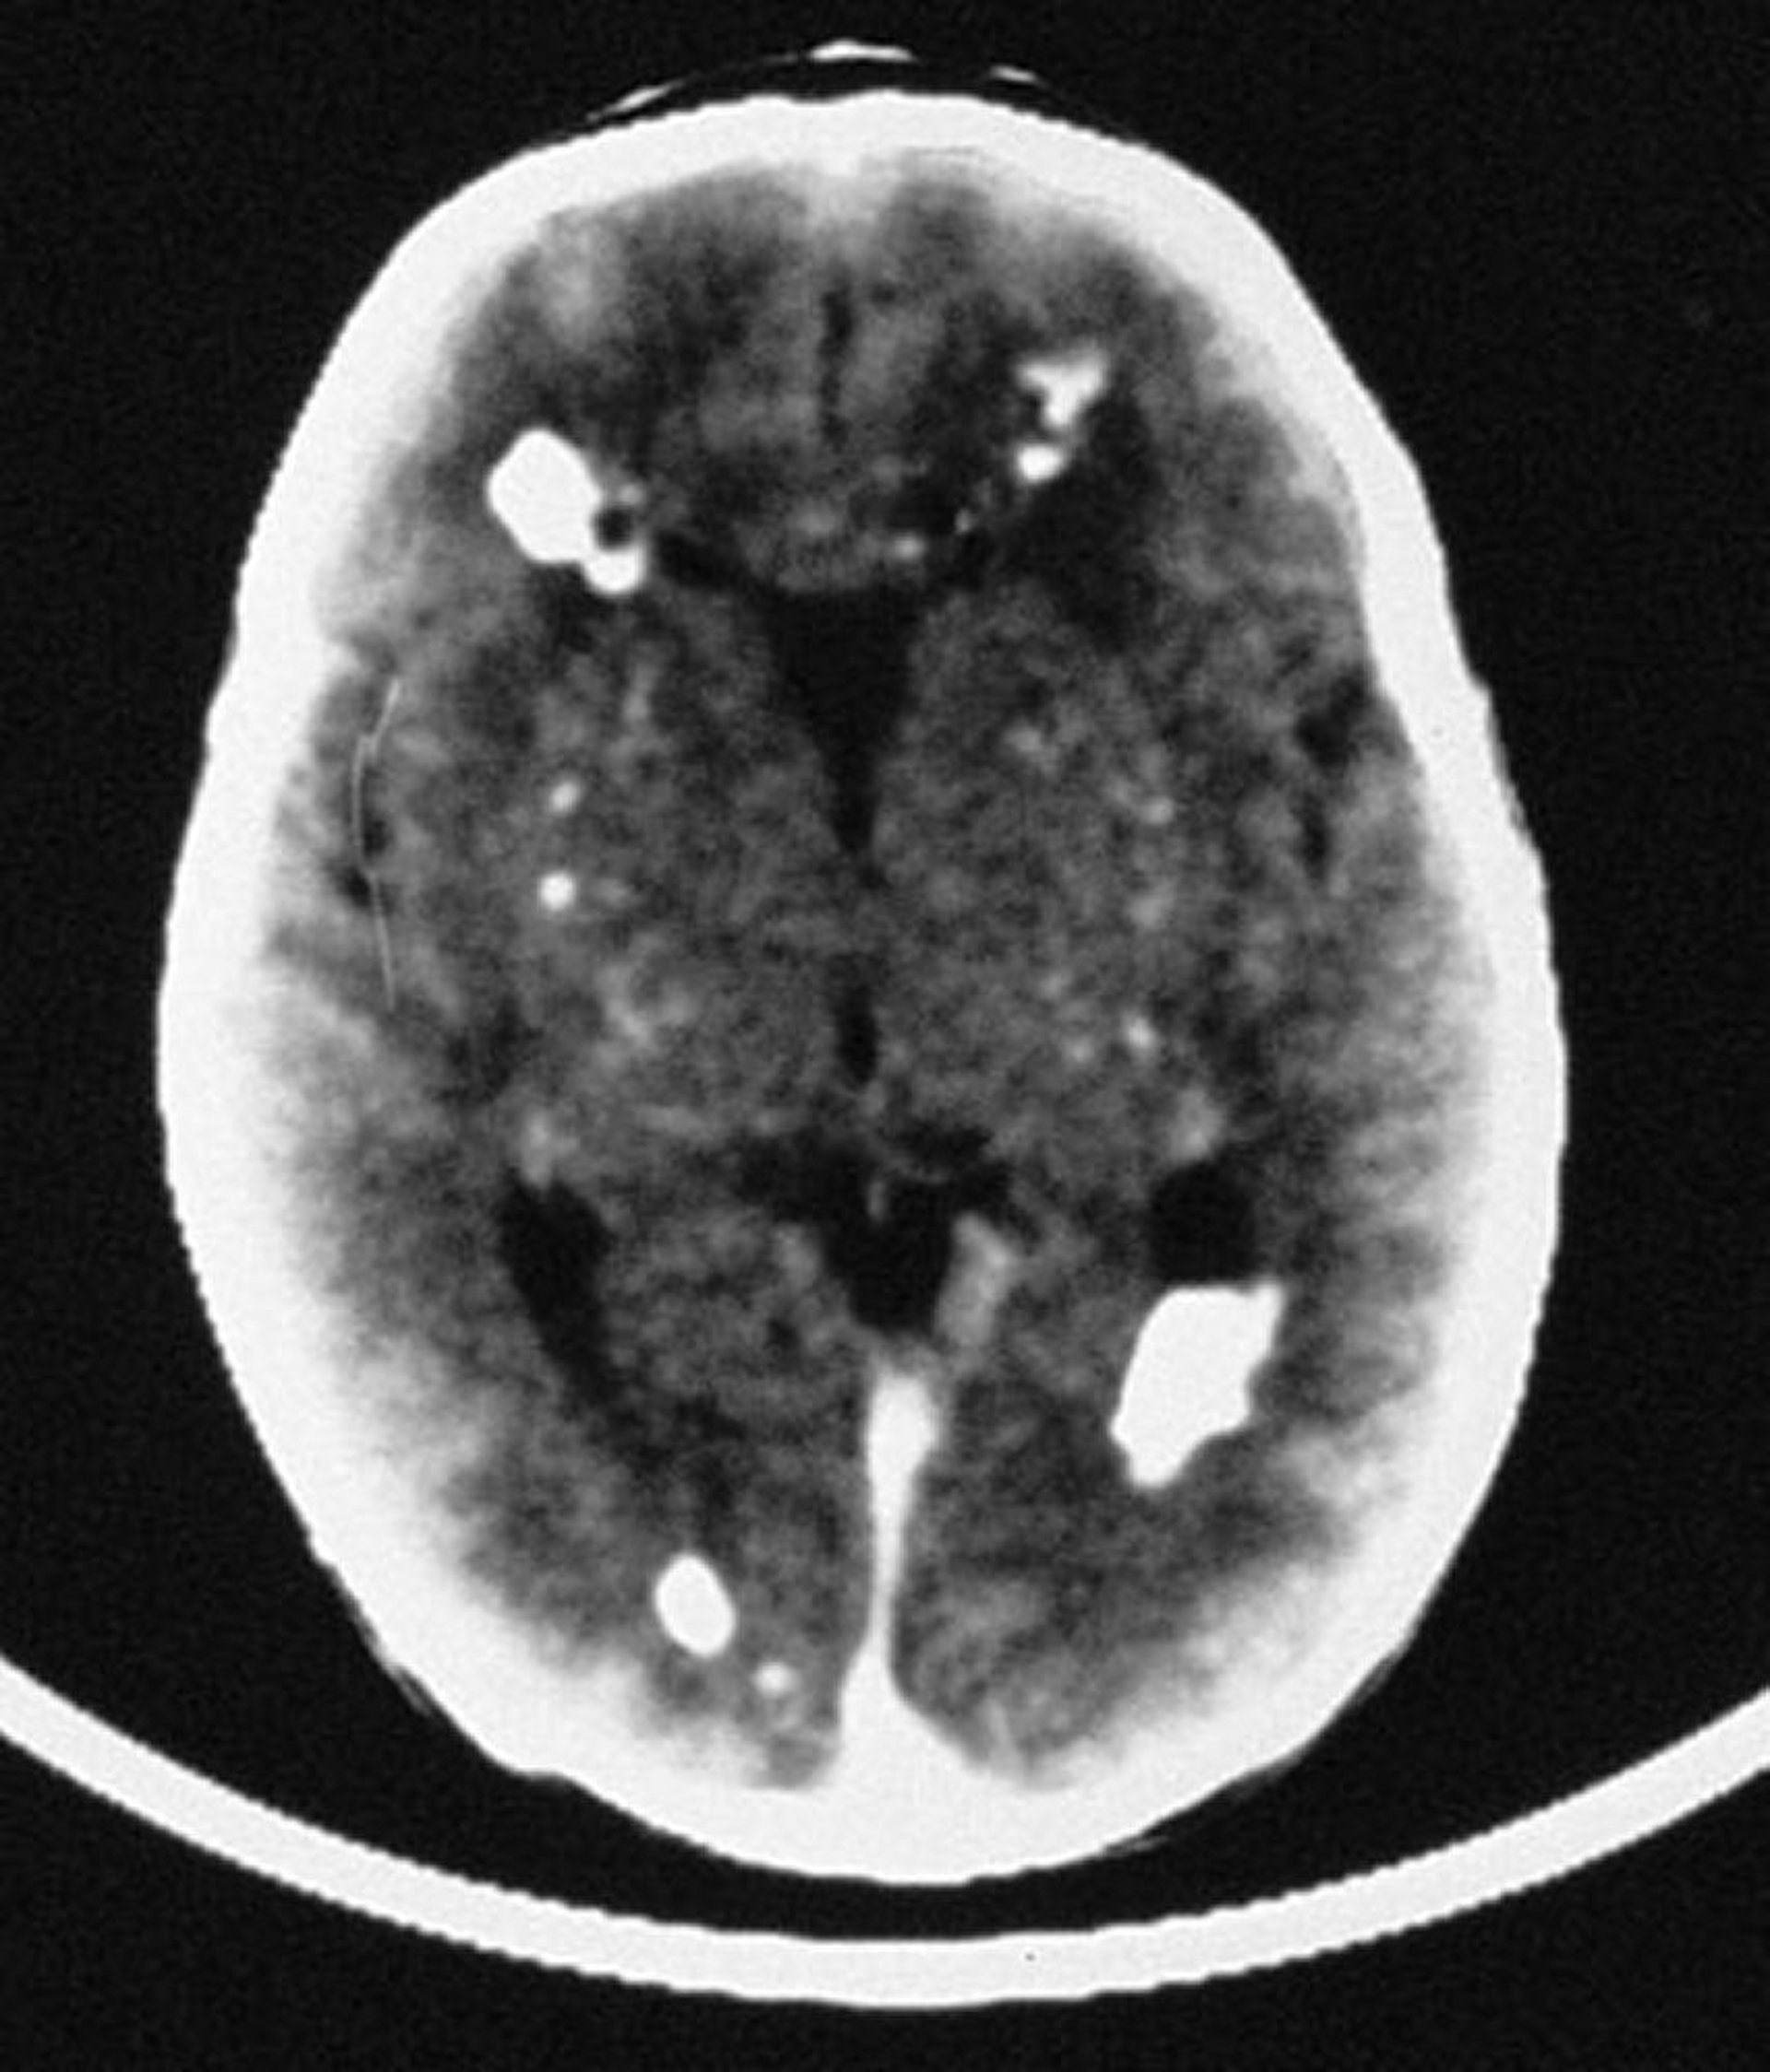

Infección congénita por citomegalovirus

En esta imagen, la tomografía computarizada revela múltiples calcificaciones intracraneales; la mayoría son periventriculares, aunque también comprometen las estructuras vasculares del cerebro.

By permission of the publisher. From Demmler G: Congenital and perinatal infections. In Atlas of Infectious Diseases: Pediatric Infectious Diseases. Edited by CM Wilfert. Philadelphia, Current Medicine, 1998.